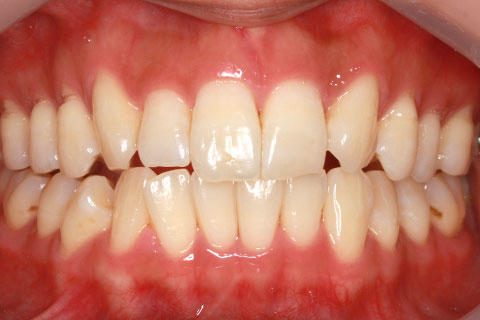

ハーフリンガル矯正3:上の歯のみ舌側矯正で治療(矯正期間24ヶ月)

- 年齢・性別

- 25歳女性

- 治療期間

- 2年0ヶ月

- 抜歯

- 上下4番抜歯

- 治療費

- 110万円

- 施術の副作用(リスク)

- 表側矯正と比較して、力学的な操作性が複雑なため、ボーイングエフェクトを起こしやすい。